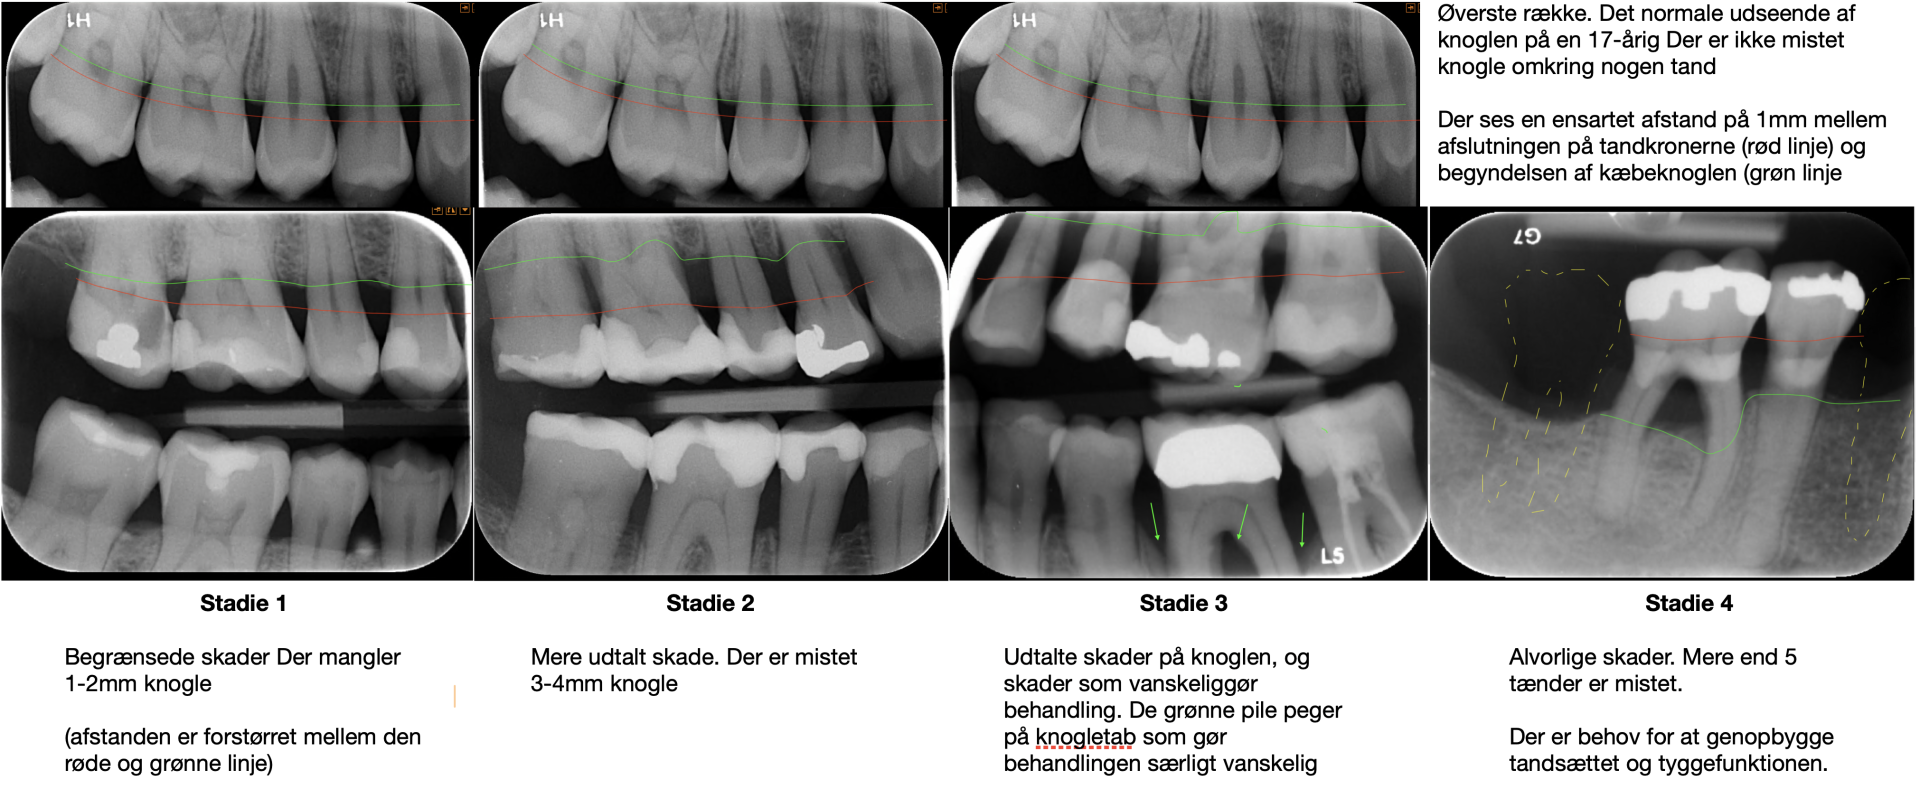

Der kan også komme gentagne smertefulde infektioner omkring dem. Det sker særligt når knoglen er forsvundet mellem rødderne på de bagerste kindtænder. Det er sket for den midterste tand på billedet til venstre. Denne tand er nu svær at behandle, fordi sygdommen er fremskreden.

I starten mangler der kun ganske lidt knogle. Med tiden udvikler sygdommen sig så der forsvinder mere og mere knogle. Tandkødslommerne bliver samtidigt dybere så bakterierne trives bedre.

På et tidspunkt når parodontosen ind mellem rødderne på de bagerste kindtænder. Nu er det meget sværere at behandle sygdommen Nogle steder løber processen hurtigere, så der dannes dyb smalle sprækker ned i knoglen som er fyldte med bakterier, men vanskelige at rense ned i. Dette vanskeliggør også behandlingen. Det er fra der af, at tænder må fjernes.

Det gælder altid om at få behandlet sygdommen så tidligt som muligt. Det skyldes, at de skader på tandkød og knogle, som sygdommen giver, ikke forsvinder igen. Når man har mistet tandkød og knogle, kommer det ikke igen. Samtidigt er behandlingen langt lettere og får et virkeligt godt resultat. Derimod er behandlingen af fremskreden sygdom svær, dyr og efterlader et resultat langt fra kroppens normale udseende.